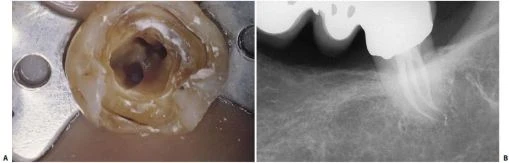

* Những trường hợp khác, chân gần có thể có một ống tủy ở chính giữa, vì vậy răng có một ống tủy ở phía xa và một ống tủy ở phía gần (hình 11.123). Để chắc chắn rằng chân gần có một ống tủy đơn, cần phải kiểm tra vị trí miệng ống tủy ở sàn buồng tủy và chụp X-quang theo nhiều hướng khác nhau. Đôi lúc có thể tìm thấy dấu hiệu thủng sàn ở phía trong xoang tủy do nha sĩ trước đã cố gắng tìm ống tủy gần trong trong khi chân gần chỉ có một ống tủy.

Hình 11.123. Răng cối lớn thứ hai hàm dưới với một ống tủy ở chân xa và một ống tủy ở chân gần. A. Xoang tủy: Hai ống tủy tại đáy của rãnh nằm giữa sàn tủy. Bên phải có dấu của mũi khoan (hướng về mặt lưỡi). Nha sĩ trước đó đã cố tìm ống tủy gần trong vốn không tồn tại. B. Phim sau điều trị: hai ống tủy nằm ở hai chân răng riêng biệt, thông nhau rõ ràng ở vị trí lỗ chóp của hai chân.